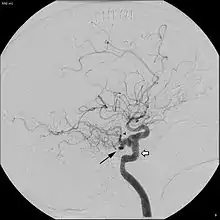

In around 0.1 to 0.6% of individuals, as sampled by magnetic resonance angiography, the trigeminal artery fails to involute and remains in the adult brain, in a condition called persistent trigeminal artery.[3] This condition is more common in women than in men, with approximately 1.8 times as many women having the condition.[6] Knowledge of a persistent trigeminal artery may be important in certain brain surgeries, as the condition is rare and an accidental cut to the artery could lead to hemorrhage.[1] Although the discovery of a persistent trigeminal artery is sometimes an incidental finding, its presence is also associated with various pathological conditions, and must therefore be considered carefully when diagnosing these conditions.[7]

A persistent trigeminal artery is associated with an increased risk of aneurysm, though some studies have suggested that this finding may be an effect of selection bias, as most individuals do not undergo the tests necessary to identify the condition.[3] Persistent trigeminal artery has been identified as a rare cause of trigeminal neuralgia, with 2.2% prevalence of persistent trigeminal artery among trigeminal neuralgia patients.[8] Surgery to move the persistent trigeminal artery away from the trigeminal nerve has been successful in treating the trigeminal neuralgia in some cases.[9] In some cases, presence of a persistent trigeminal artery concurs with hypoplasia of the basilar artery, in which case the internal carotid artery is responsible for most blood flow to the upper pons, cerebellum, midbrain, and parts of the temporal and occipital lobes, meaning that anything disrupting blood flow in the internal carotid artery could lead to ischemia in these regions.[10] In addition, persistent trigeminal artery has been associated with vertebrobasilar insufficiency, brainstem ischemia, and carotid cavernous fistulae.[2]